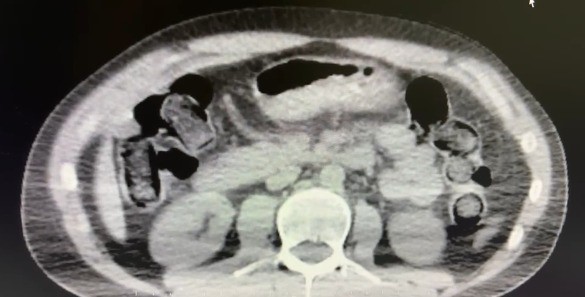

Nevşehir İl Emniyet Müdürlüğü Narkotik Suçlarla Mücadele Şube Müdürlüğü ekipleri, kentte uyuşturucu ve uyarıcı madde ticareti yapmak ve kullanmak suretiyle vatandaşları zehirleyen sokak satıcılarına yönelik çalışma başlattı. Cumhuriyet Başsavcılığı koordinesinde çalışmalarını yoğunlaştıran ekipler, şüpheliler S.B. ve O.R.’nin ’yutma yöntemi’ ile kente uyuşturucu madde sevk edeceği bilgisi üzerine operasyon düzenledi. Şüphelilerin ikametlerinde ve araçlarında yapılan aramada 101 kapsül halinde 722 gram uyuşturucu madde, 1 adet hassas terazi, uyuşturucu madde sevkiyatında yutma yönteminde kullanılan muhtelif materyaller, uyuşturucu madde ticaretinden elde edilen 20 bin 210 TL, bin 320 euro ve 10 ABD doları ele geçirildi. Emniyetteki işlemlerinin ardından adliyeye sevk edilen 2 şüpheli, çıkarıldıkları mahkemece tutuklanarak cezaevine gönderildi.